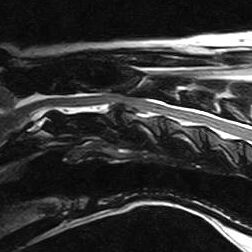

By examining an animal alone, it is impossible to determine how much of each component contributes to the signs. A myelogram, CT scan, or MRI can be used to determine the extent of spinal cord compression. The amount of bruising can, however, be extremely difficult to assess (even with specialised techniques). This concussion can sometimes be seen as spinal cord swelling.

Standard X-rays are rarely enough to diagnose a slipped disc. In a standard X-ray, only the bones of the vertebrae are visible, not the discs between them or the spinal cord. Conventional X-rays can sometimes reveal disc degeneration without the animal showing any symptoms. Only myelography (X-rays taken after injection of dye around the spinal cord), CT (computed tomography) or MRI (magnetic resonance imaging) can reliably diagnose a slipped disc. Tests such as these help to determine whether there is a slipped disc, where it is located, and if there are any other causes of spinal pain or paralysis.

In type-II disc disease, the outer ligament (annulus fibrosus) protrudes or bulges over time. Thickening is thought to occur due to ligament tears over time, and as the ligament repairs itself it thickens (a process called hypertrophy). As the dorsal part of the annulus fibrosus thickens, it presses up against the spinal cord (disc protrusion). The lower neck, mid-back, and lower back are the regions of the spinal column that are more likely to experience disc degeneration. This is a slowly progressive condition that most often affects dogs and cats 5-12 years old of mid to large breeds